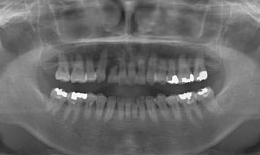

インプラント症例(3)46歳 女性

治療前